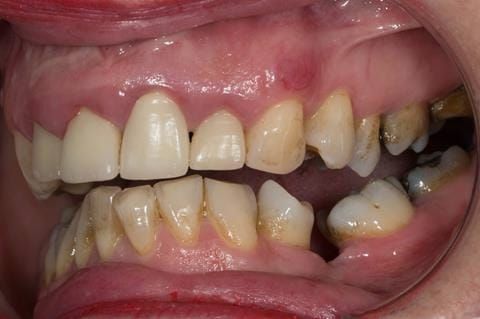

Provision of a maxillary cobalt chromium based partial denture/protective occlusal splint in a heavily restored dentition

- UR2 peri-radicular periodontitis with a peri-radicular area on the root apex. Retrograde amalgam filling from a previous apicectomy. No visible root canal or root canal filling. Large circumferential marginal gap between the crown and tooth. Large post and core present. Very little tooth structure remaining resulting in a fragile tooth with increased potential for fracture.

- UR1 peri-radicular periodontitis with a small peri-radicular area on the root apex with wide blunderbuss apex. Radio-opaque root canal filling present approximately 3 mm short of the radiographic apex. Large circumferential marginal gap between the crown and tooth. Large post and core present. Very little tooth structure remaining resulting in a fragile tooth with increased potential for fracture.

- UL1 peri-radicular periodontitis with a peri-radicular area on the root apex. Retrograde amalgam filling from a previous apicectomy. Visible root canal space with no sign of root canal filling. Large circumferential marginal gap between the crown and tooth. Large post and core present. Very little tooth structure remaining resulting in a fragile tooth with increased potential for fracture.

- UL2 peri-radicular periodontitis with a peri-radicular area on the root apex. No visible root canal or root canal filling. Large circumferential marginal gap between the crown and tooth. Large post and core present. Very little tooth structure remaining resulting in a fragile tooth with increased potential for fracture.

- High smile line showing gum above gingival zeniths of upper front teeth when smiling. Aesthetic failure of the upper four incisors with inflammation of the gingivae and mis-match of the gingival zenith levels.

- Other than the maxillary incisors the remaining dentition was in marginally better condition being moderately to heavily restored. Many will probably require replacement and restoration from time to time mainly from wear and tear owing to occlusal forces.

Following consultation and second discussion appointment the patient chose to have option 3 namely, a maxillary cobalt chromium based partial denture/protective occlusal splint. The clinical situation and treatment process is shown in detail below with photographs. The patient was successfully rehabilitated with this and her quality of life considerably improved. The clinical work was provided by Finlay and the technical work by Rowan.